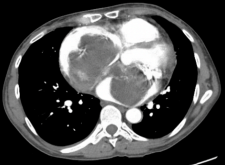

CaseReport_Biatrial Myxoma_Fig3